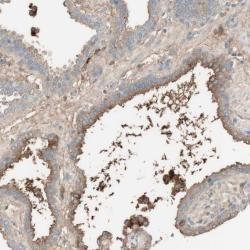

Supportive validation

- Experimental details

- Immunohistochemical staining of human prostate shows cytoplasmic positivity in glandular cells.

- Validation comment

- Staining pattern consistent with experimental and/or bioinformatic data.